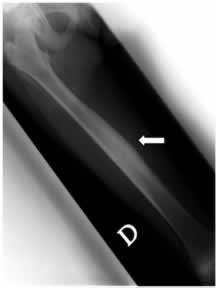

A distanza di un anno (2004) C. ritorna nuovamente alla nostra attenzione per la comparsa di febbricola accompagnata da dolori agli arti inferiori, in particolare a destra, con indici di flogosi aumentati e rilievo obiettivo di sfumato deficit di forza all'arto inferiore destro, su base antalgica .L'ecografia e la radiografia dell'arto inferiore destro mostrano rispettivamente un minimo versamento articolare a livello della coxo-femorale e un aspetto del femore, sempre a destra, di marcato ispessimento della corticale ossea, come da reazione periostale, con una relativa iperdiafania della spongiosa. (figura 2)

Questi reperti associati al dato scintigrafico dell'anno precedente di ipercaptazione lungo tutto il femore, con artrite e risposta ai FANS, orientano verso un quadro di periostite ricorrente. Viene comunque eseguita biopsia ossea che esclude una malignit� .

Figura 2: radiogramma del femore che mostra, al III medio, marcato aumento di spessore della corticale ossea sul versante interno